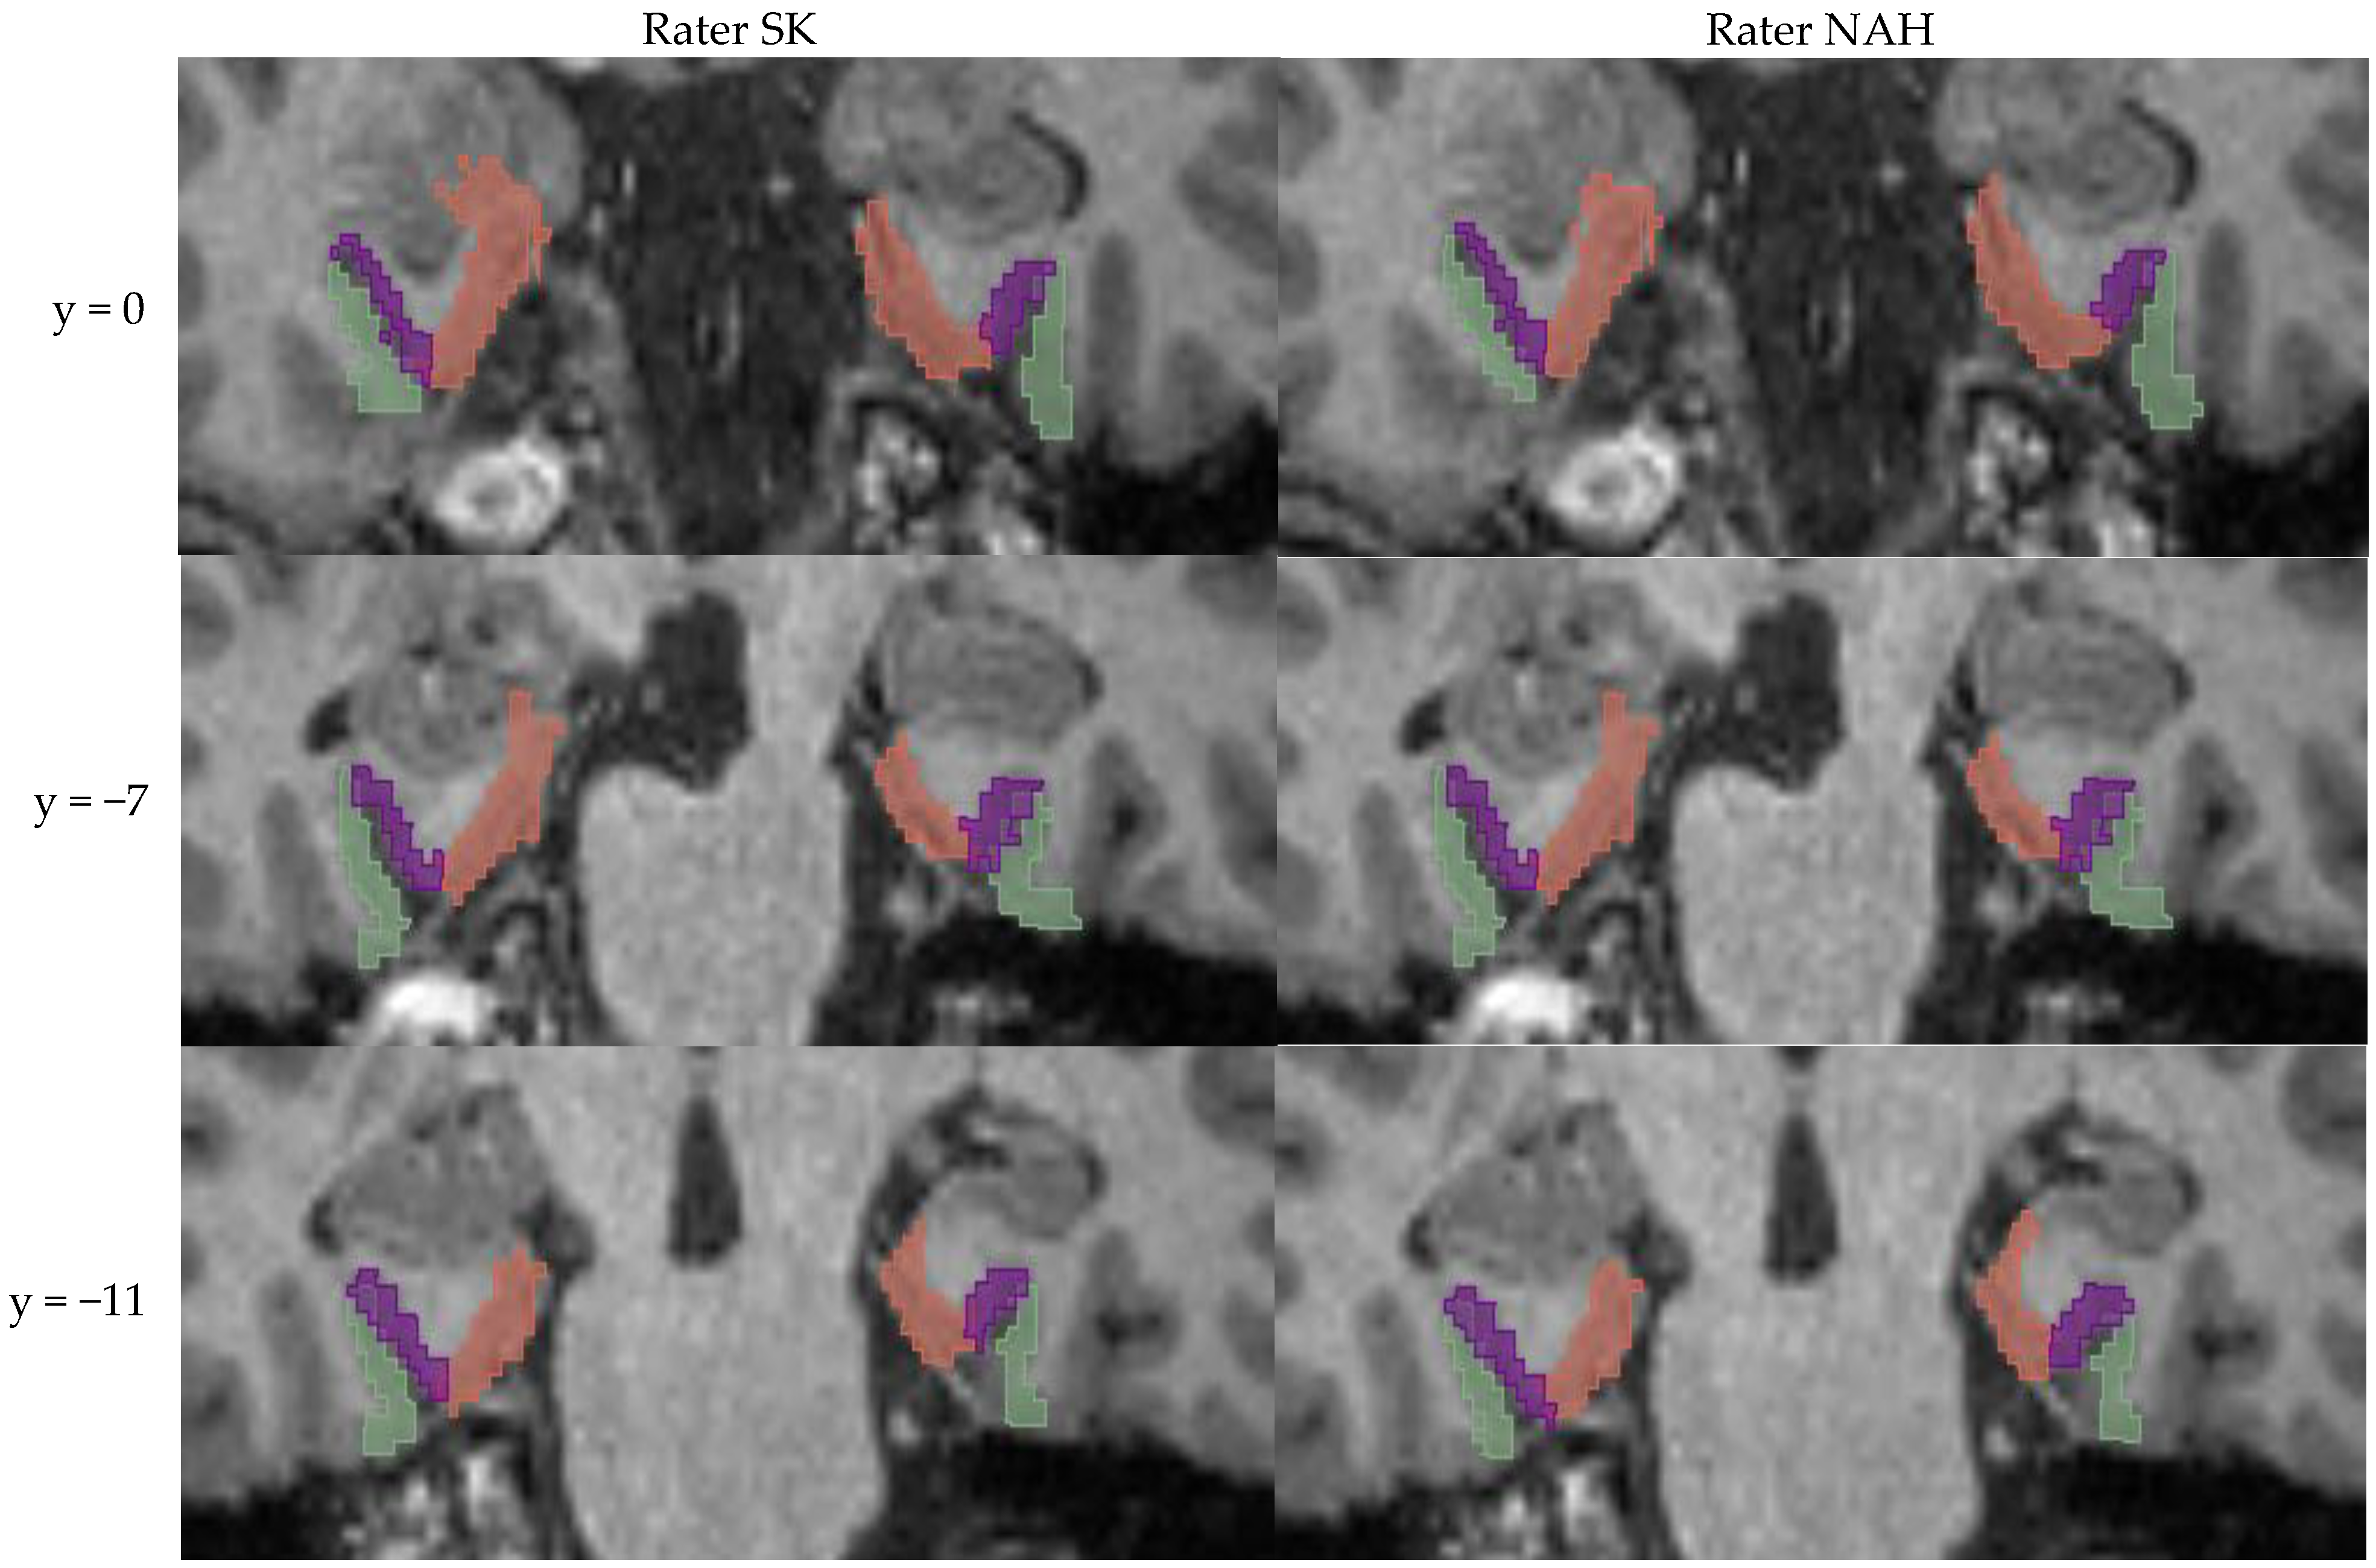

2.4. Manual Segmentation